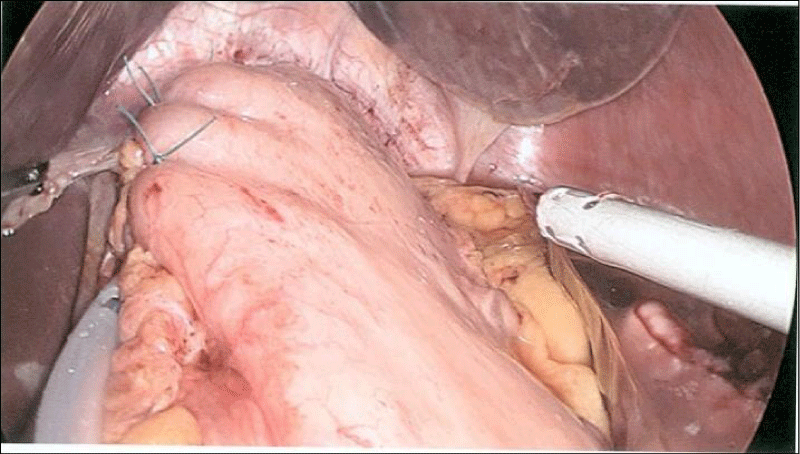

An intraoperative OGD was performed (Figure 3) and showed a small para oesophageal hernia with normal mucosa of oesophagus, stomach and duodenum. During laparoscopy, the hernia was reduced and a para oesophageal extraluminal 4cm multilobulated tumour was visualised in the left posterior mediastinum (Figure 4). After mobilisation of the greater curvature of stomach and lower 1/3 of oesophagus, the tumour was delivered into the abdominal cavity (Figure 5). The tumour was enucleated from the muscular wall without breaching the mucosa and an air leak test did not show any leak. After removing the tumour, a diverticulum of oesophageal mucosa remained (traction diverticulum caused by the tumour) just above the Gastro-Oesophageal Junction (GOJ). It was decided to leave it to regress with time. The diaphragmatic crura were closed with a mattress suture and an anterior Dor fundoplication was performed (Figure 6). The tumour was retrieved using Espiner bag (Espiner medical LTD).